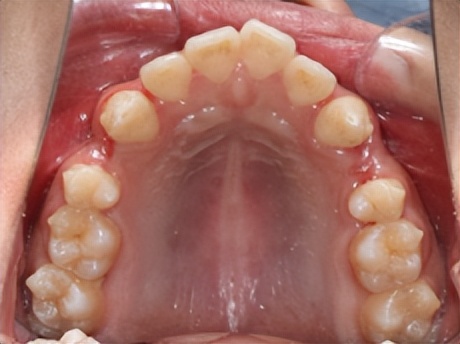

矫正经典拔牙模式: 拔除上下左右4颗双尖牙

为了实现矫治后上下牙列能有良好的尖窝咬合关系,通常上下牙列都需要拔牙。尽管有些病例看上去排齐牙列或内收前牙需要的间隙并不多,但是为了达到矫治后牙弓的左右对称,上下中线居中对齐,所以需要左右两侧同时拔牙。

因此,临床最常规的矫治方案是上下左右各拔除一颗双尖牙,共4颗牙齿。当然,如果口腔内恰恰有龋坏或缺失的牙齿,医生则会根据诊断分析的结果调整拔牙方式。